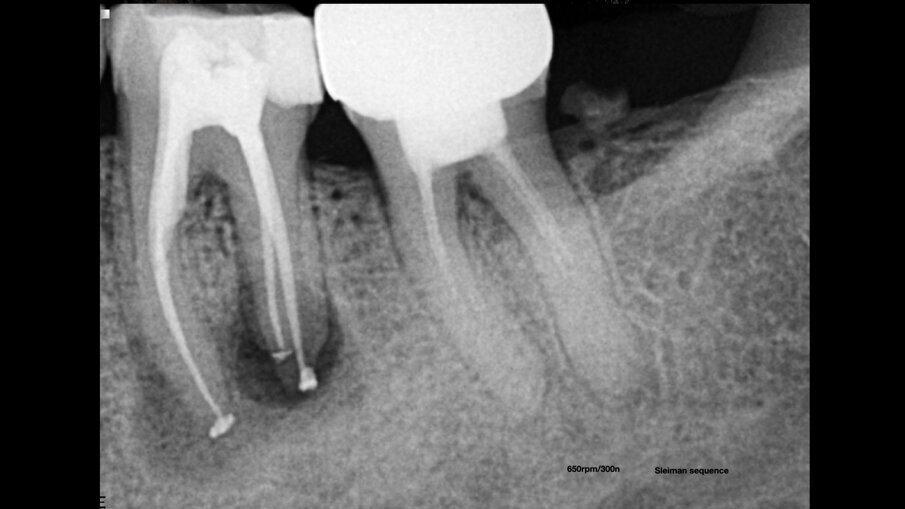

Irigacija u endodonciji je široko pogrešno shvaćena, ali je tako jednostavna kada razumemo hemikalije koje koristimo i šta je naš cilj i kako ga postići. Dajući svakoj hemikaliji posao ili cilj koji bi trebalo da postigne i razumevanjem hemijskih interakcija – irigacija je stvar bavljenja različitim vrstama hemikalija – možemo postići bolju, mnogo bržu i sigurniju dezinfekciju kanala korena zuba. Pre upotrebe natrijum-hipohlorita, trebalo je do 20-30 minuta vremena, a sada dezinfekcija traje nekoliko sekundi. Nivo bakterija od nule je na dohvat ruke i nije potrebna posebna nauka da bi se to postiglo. Nula bakterija znači da možemo imati bolju prognozu za lečenje kanala korena zuba i veće stope uspeha našeg ponovnog lečenja, a omogućava nam takođe tretman u jednoj poseti i da nije potrebno postavljati privremene “zavoje” – mit o kalcijum hidroksidu više ne postoji. Kao demonstraciju, razmotrite slučaj nekrotičnog molara sa relativno velikom radiolucencijom koji smo lečili tretmanom kanala korena u jednoj poseti prema našem protokolu irigacije (Sl. 4–6).

Sl.4: Nekrotični molar sa relativno velikom radiolucencijom. Sl.5: Postoperativna radiografija neposredno nakon tretmana. Sl.6: Kontrolni Rtg snimak nakon godinu dana od tretmana koji pokazuje potpuno zarastanje.

Fig. 4: Necrotic molar with a relatively large radiolucency.